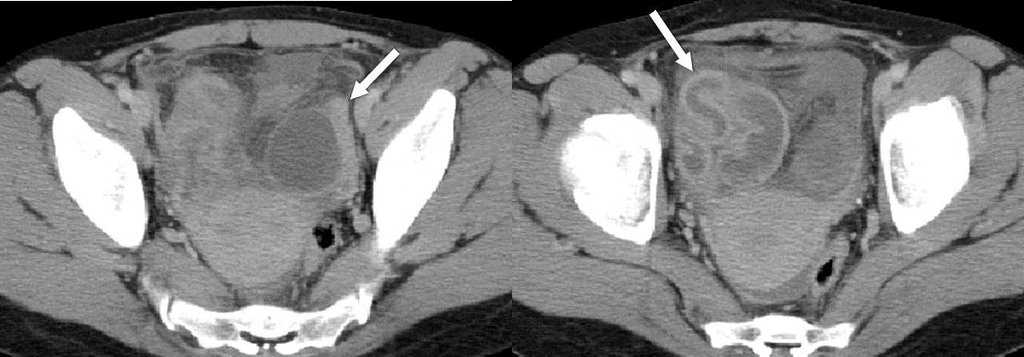

詳解

破題關鍵

這題的解題核心在於辨識電腦斷層影像中,箭頭所指的骨盆腔複雜性病灶,結合病人發燒和下腹痛的臨床症狀,判斷最可能的診斷。圖片中可見一個邊緣厚實、明顯強化的囊性病灶,內部有不均勻的液體或膿液,這是輸卵管卵巢膿瘍的典型影像特徵。

選項拆解